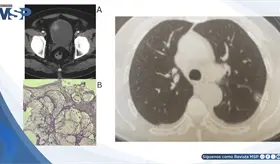

El VIH debilitó gravemente el sistema inmunológico del paciente (CD4 162), permitiendo que una bacteria poco común como Rhodococcus causara un absceso pulmonar severo que simuló tuberculosis y no respondió al tratamiento habitual.